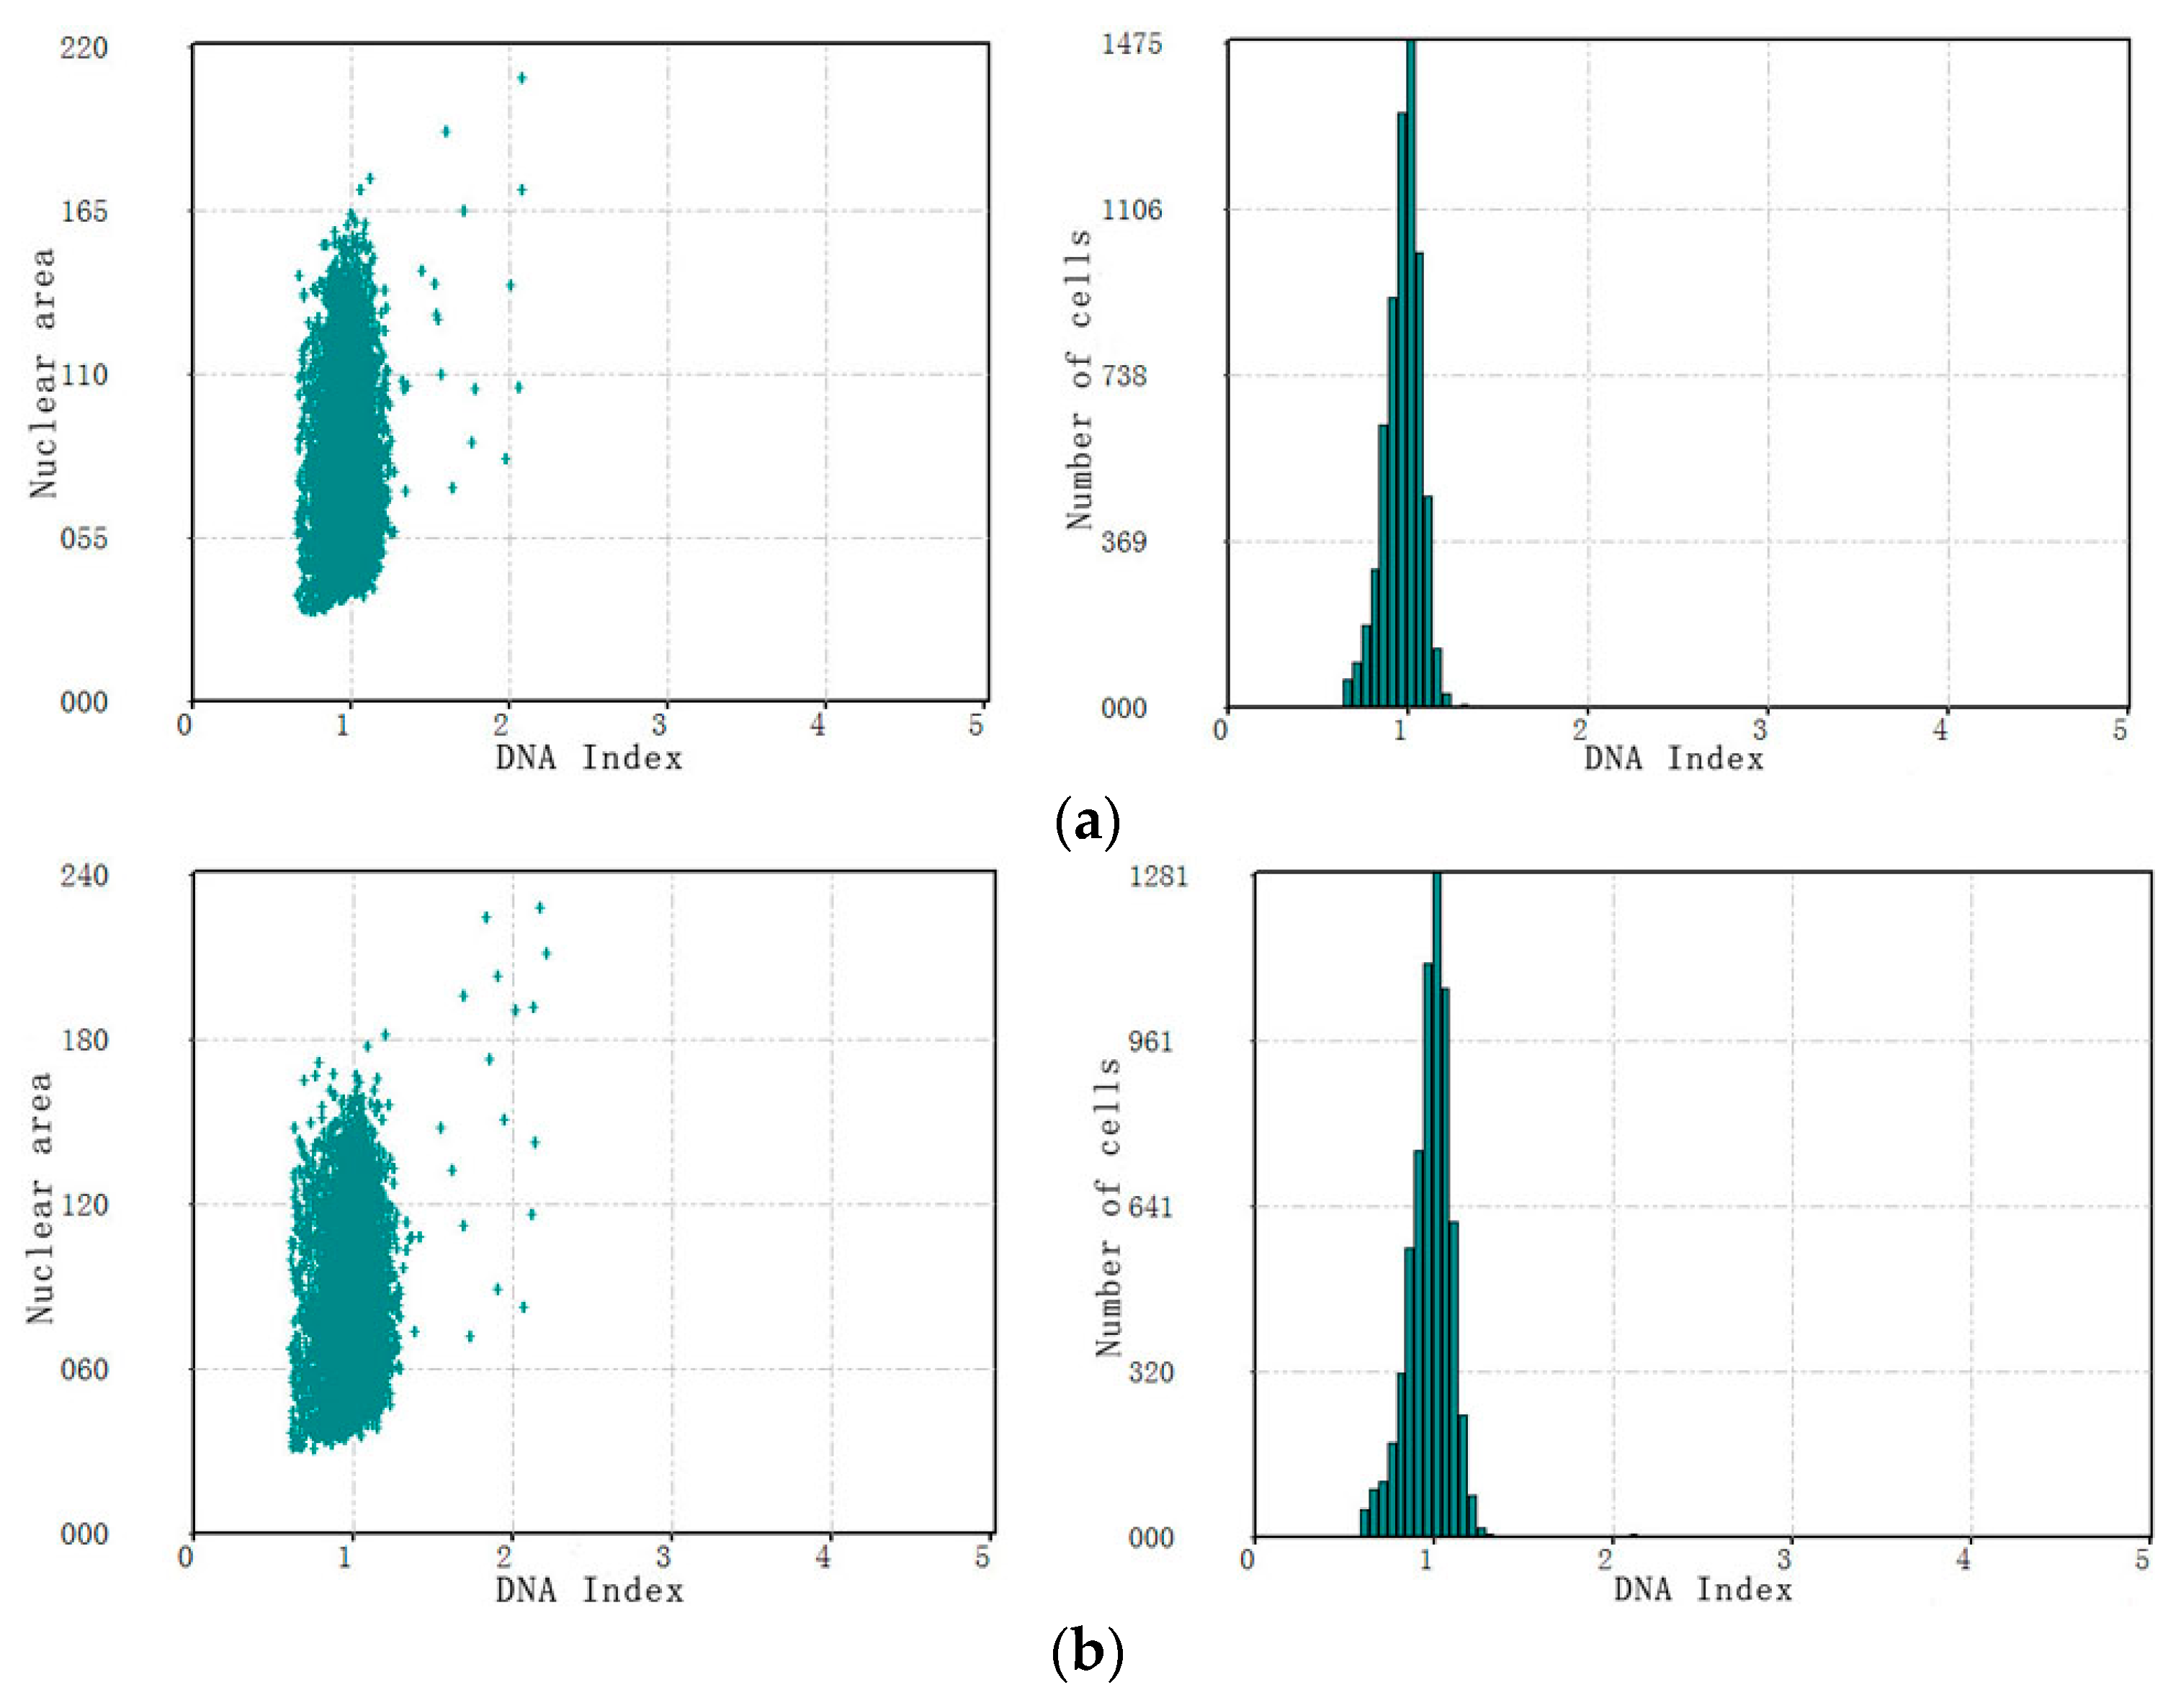

3.3. The Performance of Cervical Cell Screening